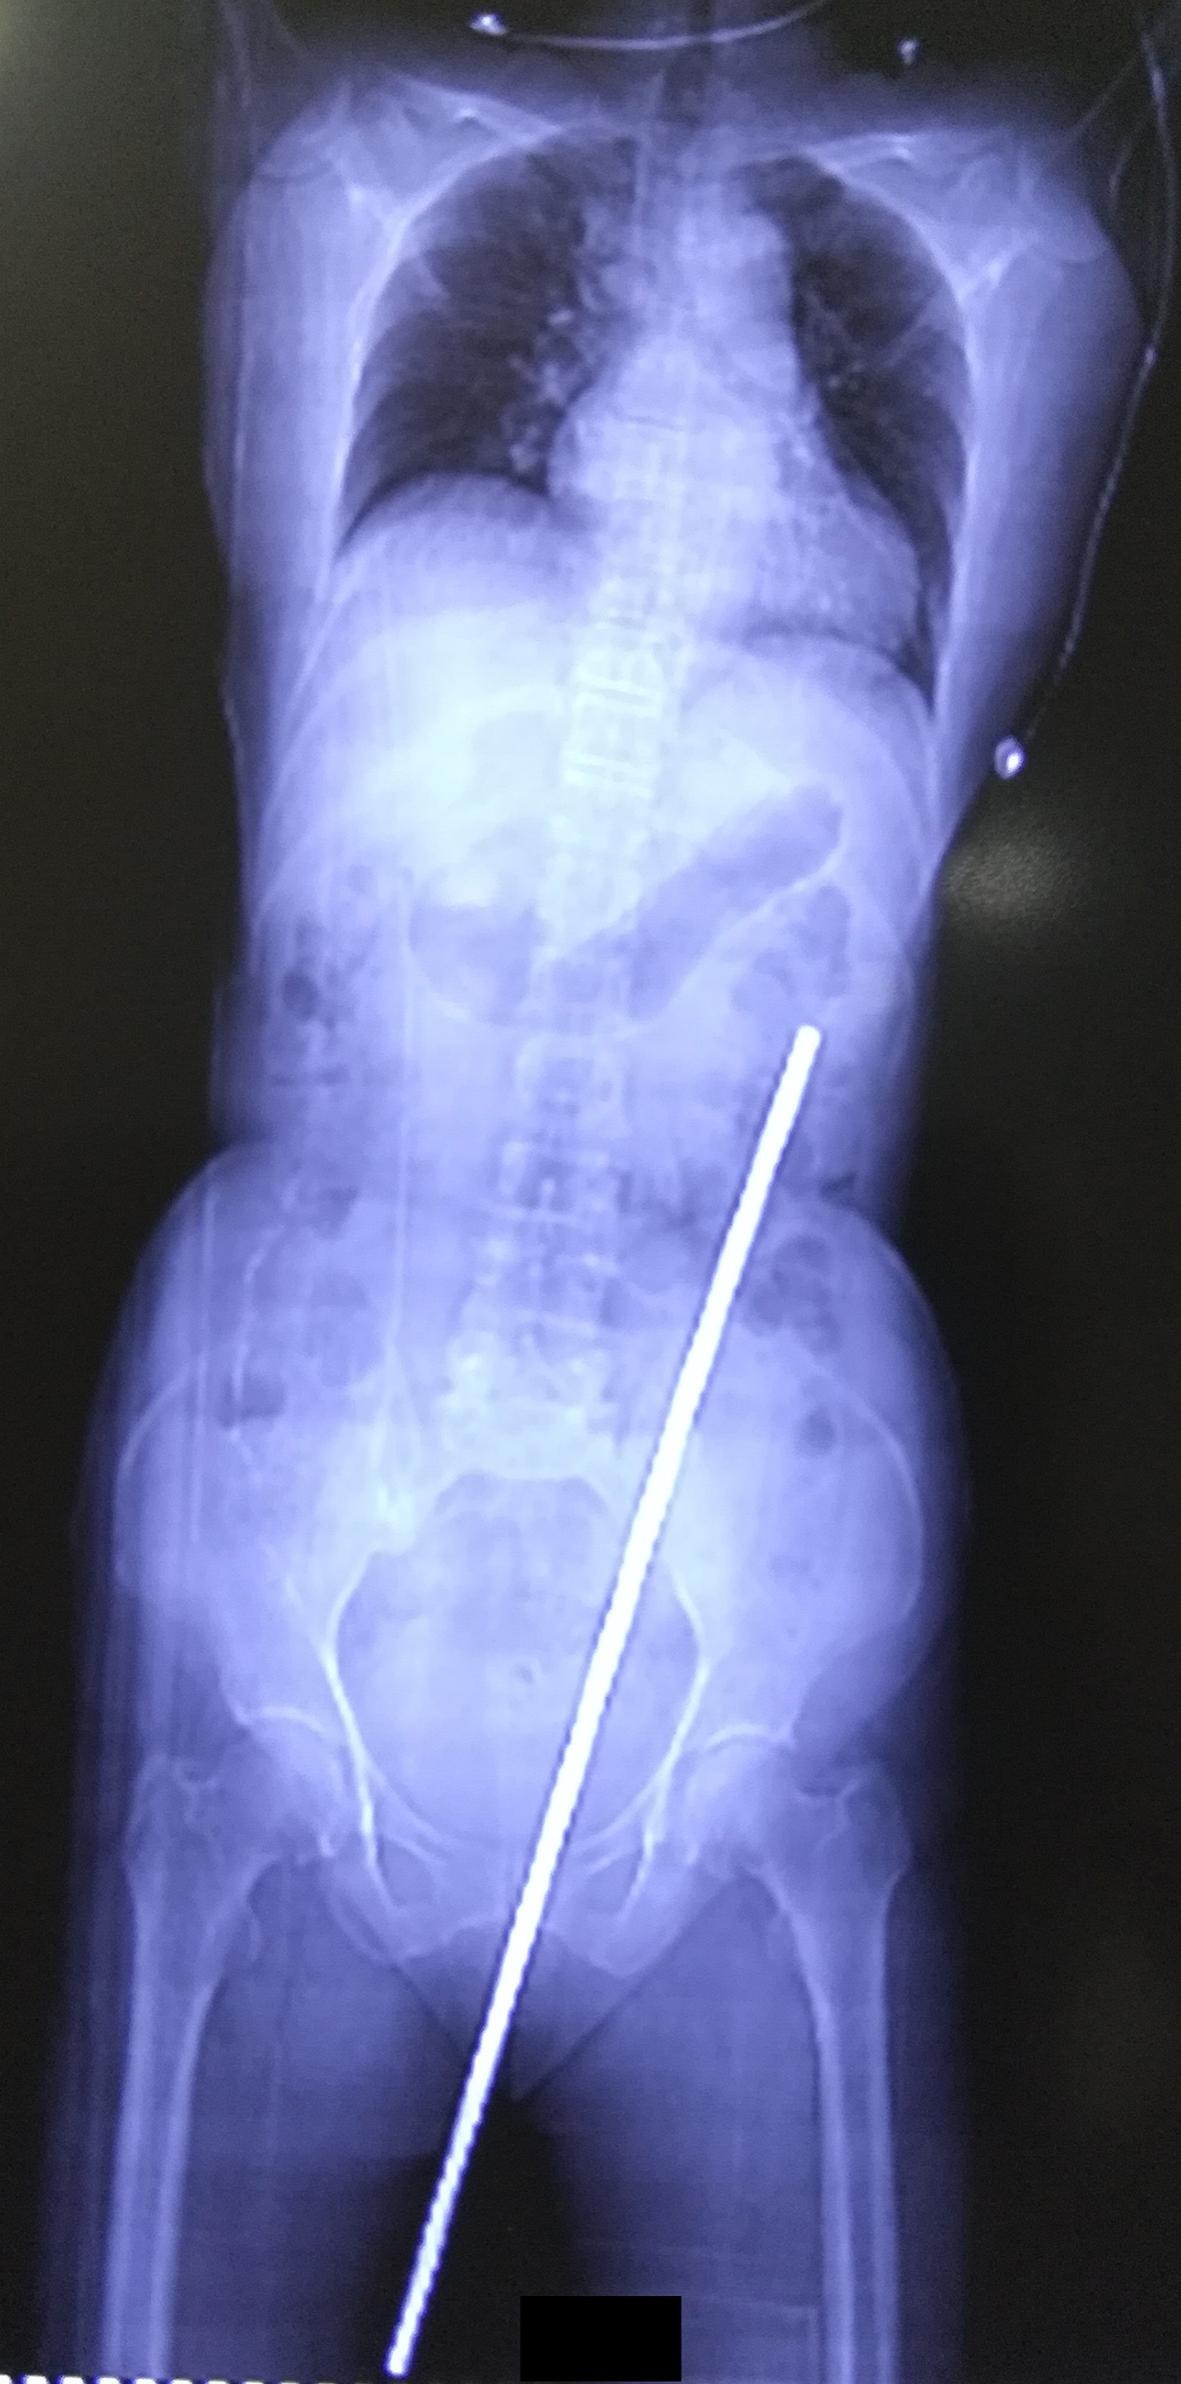

Η γυναίκα βρισκόταν στο χωράφι που βρίσκεται δίπλα στο σπίτι της, φροντίζοντας τις αγελάδες της, όταν η μοίρα της έπαιξε ένα τρομακτικό παιχνίδι. Μία σκουριασμένη μεταλλική βέργα, μήκους σχεδόν 60 εκατοστών, είχε τοποθετεί στο έδαφος του χωραφιού, προκειμένου να στηρίξει αναρριχώμενα φυτά. Η γυναίκα, ενώ φρόντιζε τις αγελάδες της, έχασε την ισορροπία της λόγω της «ανησυχίας» μιας αγελάδας, καθώς ήταν δεμένη μαζί της με ένα σχοινί στον καρπό της, και κάθισε επάνω στη βέργα, με αποτέλεσμα να εισέλθει από τον πρωκτό της, να διαπεράσει το έντερό της και να επεκταθεί πίσω από την κοιλιακή κοιλότητα.

Η κατάσταση της γυναίκας ήταν σοβαρή, καθώς η βέργα είχε προκαλέσει διάτρηση του εντέρου και είχε εισχωρήσει στον χώρο πίσω από την κοιλιακή κοιλότητα. Παρά τη σοβαρότητα του ατυχήματος, η βέργα δεν κατάφερε να προκαλέσει βλάβες σε αιμοφόρα αγγεία και ζωτικά όργανα, κάτι που αναφέρθηκε στην ιατρική έκθεση για την περίπτωση της.

Η χειρουργική επέμβαση, που διήρκεσε δύο ώρες, περιλάμβανε την αφαίρεση της ράβδου μέσω του πρωκτού και την αποκατάσταση της διάτρησης. Μετά την επέμβαση, η γυναίκα είχε ναυτία και κοιλιακούς πόνους ενώ δεν μπορούσε να περπατήσει. Ωστόσο, η ανάρρωσή της προχώρησε χωρίς προβλήματα και, μετά από περίπου δέκα ημέρες, κατάφερε να επιστρέψει στο σπίτι της.